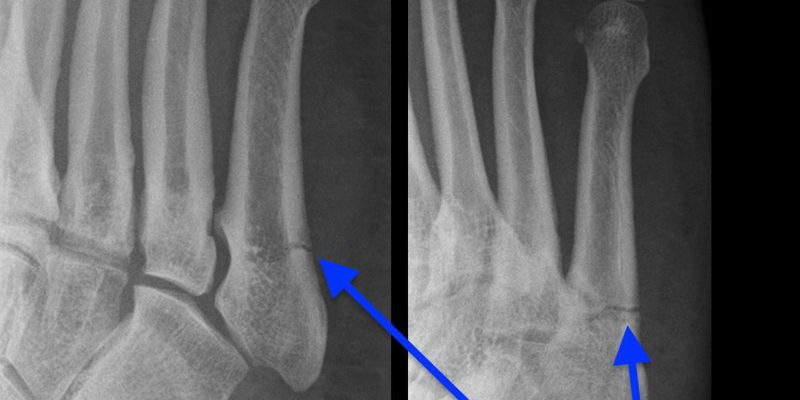

Uszkodzenia zmęczeniowe kości powstają wyniku przekroczenia bariery/granicy wytrzymałości kości, w wyniku powtarzalnych obciążeń. Celowo używam słowa uszkodzenie, a nie złamanie, gdyż obecnie wczesna diagnostyka pozwala wykryć sytuacje przed wystąpieniem złamania. Jest to bowiem powolny, rozłożony w czasie proces, rozpoczynający się od mikroskopijnych uszkodzeń, powszechnie określanych jako reakcja stresowa kości, do pełnego złamania na najbardziej skrajnym końcu spektrum.